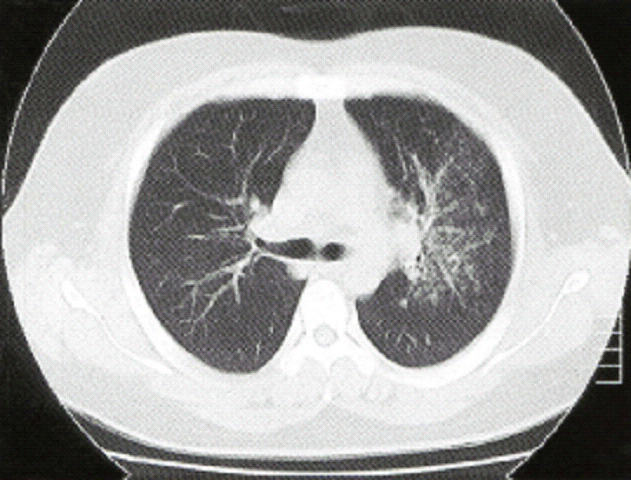

胸部エックス線写真と胸部単純CTを示す。

マイコプラズマ肺炎 マイコプラズマ肺炎CT

また、画像、特にCTでは気管支壁の肥厚がみられ、気管支病変が考えられます。

中枢側優位の所見で、小葉中心性の陰影かどうかははっきりしませんが、マイコで矛盾ない所見です。